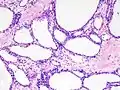

Micrograph showing a pancreatic serous cystadenoma. H&E stain.

Pancreatic serous cystadenoma is a benign tumour of the pancreas.[2] It is usually solitary and found in the body or tail of the pancreas, and may be associated with von Hippel–Lindau syndrome.[2]

In contrast to some of the other cyst-forming tumors of the pancreas (such as the intraductal papillary mucinous neoplasm and the pancreatic mucinous cystadenoma), serous cystic neoplasms are almost always entirely benign. There are some exceptions; rare case reports have described isolated malignant serous cystadenocarcinomas.[3] In addition, serous cystic neoplasms slowly grow, and if they grow large enough they can press on adjacent organs and cause symptoms.

Pathologists classify serous cystic neoplasms into two broad groups. Those that are benign, that have not spread to other organs, are designated "serous cystadenoma".[5] Serous cystadenomas can be further sub-typed into microcystic, oligocystic (or macrocystic), solid, mixed serous-endocrine neoplasm, and VHL-associated serous cystic neoplasm. This latter classification scheme is useful because it highlights the range of appearances and the clinical associations of these neoplasms. Serous cystic neoplasms that have spread ("metastasized") to another organ are considered malignant and are designated "serous cystadenocarcinoma".